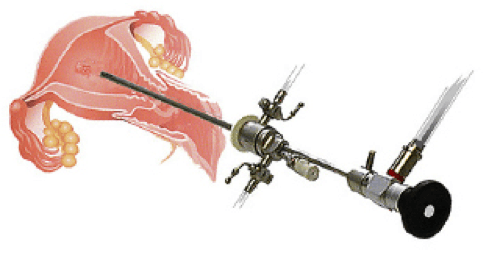

ByRL HYSTEROSCOPY INSTRUMENTS

Hysteroscopy is the clinical examination of the uterine cavity by endoscopy procedure with access through the cervix. It allows for the diagnosis of intrauterine pathology and serves as a method for surgical intervention (operative hysteroscopy). Its a minimal invasive procedure done by Gynaecologists.

Various instruments have been used to carry out Hysteroscopic procedure :- Diagnostic Hysteroscopy Sheath

- Operative Hysteroscopy Sheath

- Rat Toothed Alligator Hysteroscopic Grasper

- Hysteroscopic Scissors etc.